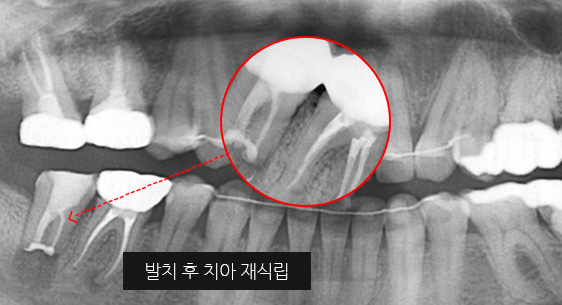

심한 염증으로 치조골이 광범위하게 소실, 아래쪽 신경관이 가까이 있어 치근단수술이 불가능한 상태, 타 병원에서 임플란트 진단을 받았지만,

고운미소치과에서 치아를 발치하고 뿌리 쪽 염증을 제거한 후 발치한 치아를 다시 심는 치아재식술을 시행하였습니다.

기존 신경치료 부위에 염증과 치조골이 소실되고 있는 상태

치아를 발치하고 염증을 제거, MTA로 충전하고 치아를 다시 심음. (난이도 최상)